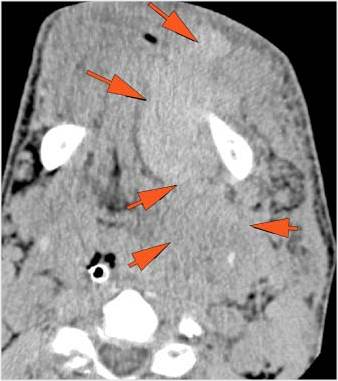

34-year-old male in the ER following an altercation with possible mandibular or other facial fractures due to craniofacial trauma.Exam

34-year-old male in the ER following an altercation with possible mandibular or other facial fractures due to craniofacial trauma.